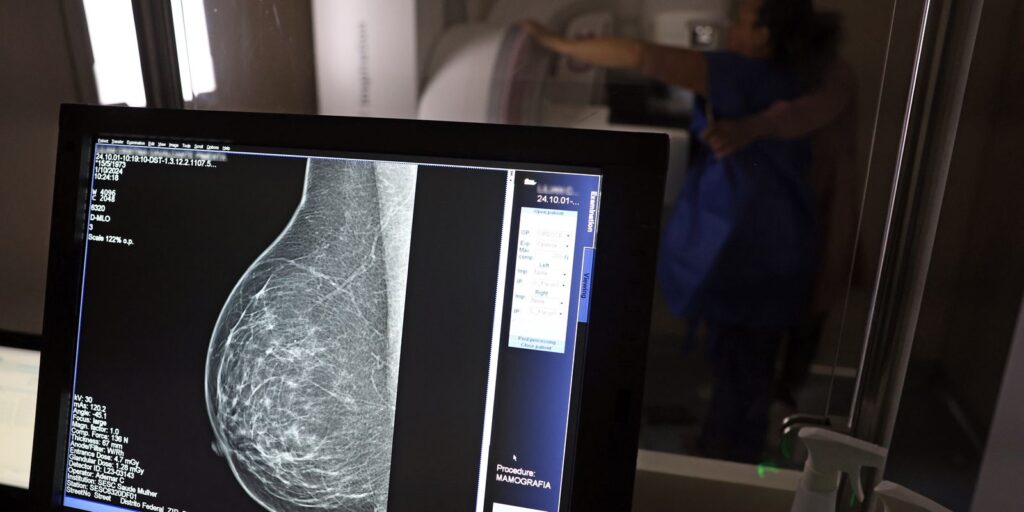

O direito já estava incluído na CLT desde 2018. A partir de agora, as empresas passam a ser obrigadas a divulgar essa informação, além de outras relacionadas a campanhas oficiais de vacinação contra o HPV e sobre o acesso a serviços de diagnósticos de cânceres de mama, próstata e de colo do útero.

O texto estende o uso das folgas também para a realização de exames preventivos do HPV, além dos de câncer que já estavam previstos na legislação anterior. A a Lei 15.377 foi sancionada pelo presidente Luiz Inácio Lula da Silva, e publicada na edição do Diário Oficial da União (DOU).